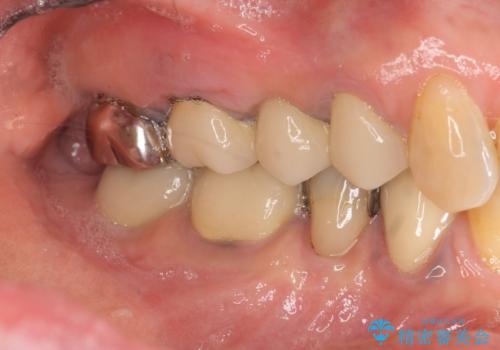

- 「噛むと歯に痛みを感じる、噛めない。」、と痛みの改善を希望され来院されました。

X線写真検査を行ったところ、ブリッジ支台の歯が破折(割れている状態)し抜歯が必要な状態です。

抜歯をしたのちしっかりと咬合力を回復し前後の歯を守るためにも、入れ歯やブリッジではなくインプラントによる咬合機能回復を計画します。

インプラント治療が終了し、しっかりと咬合機能が回復しまた食事が楽しめるようになりました。